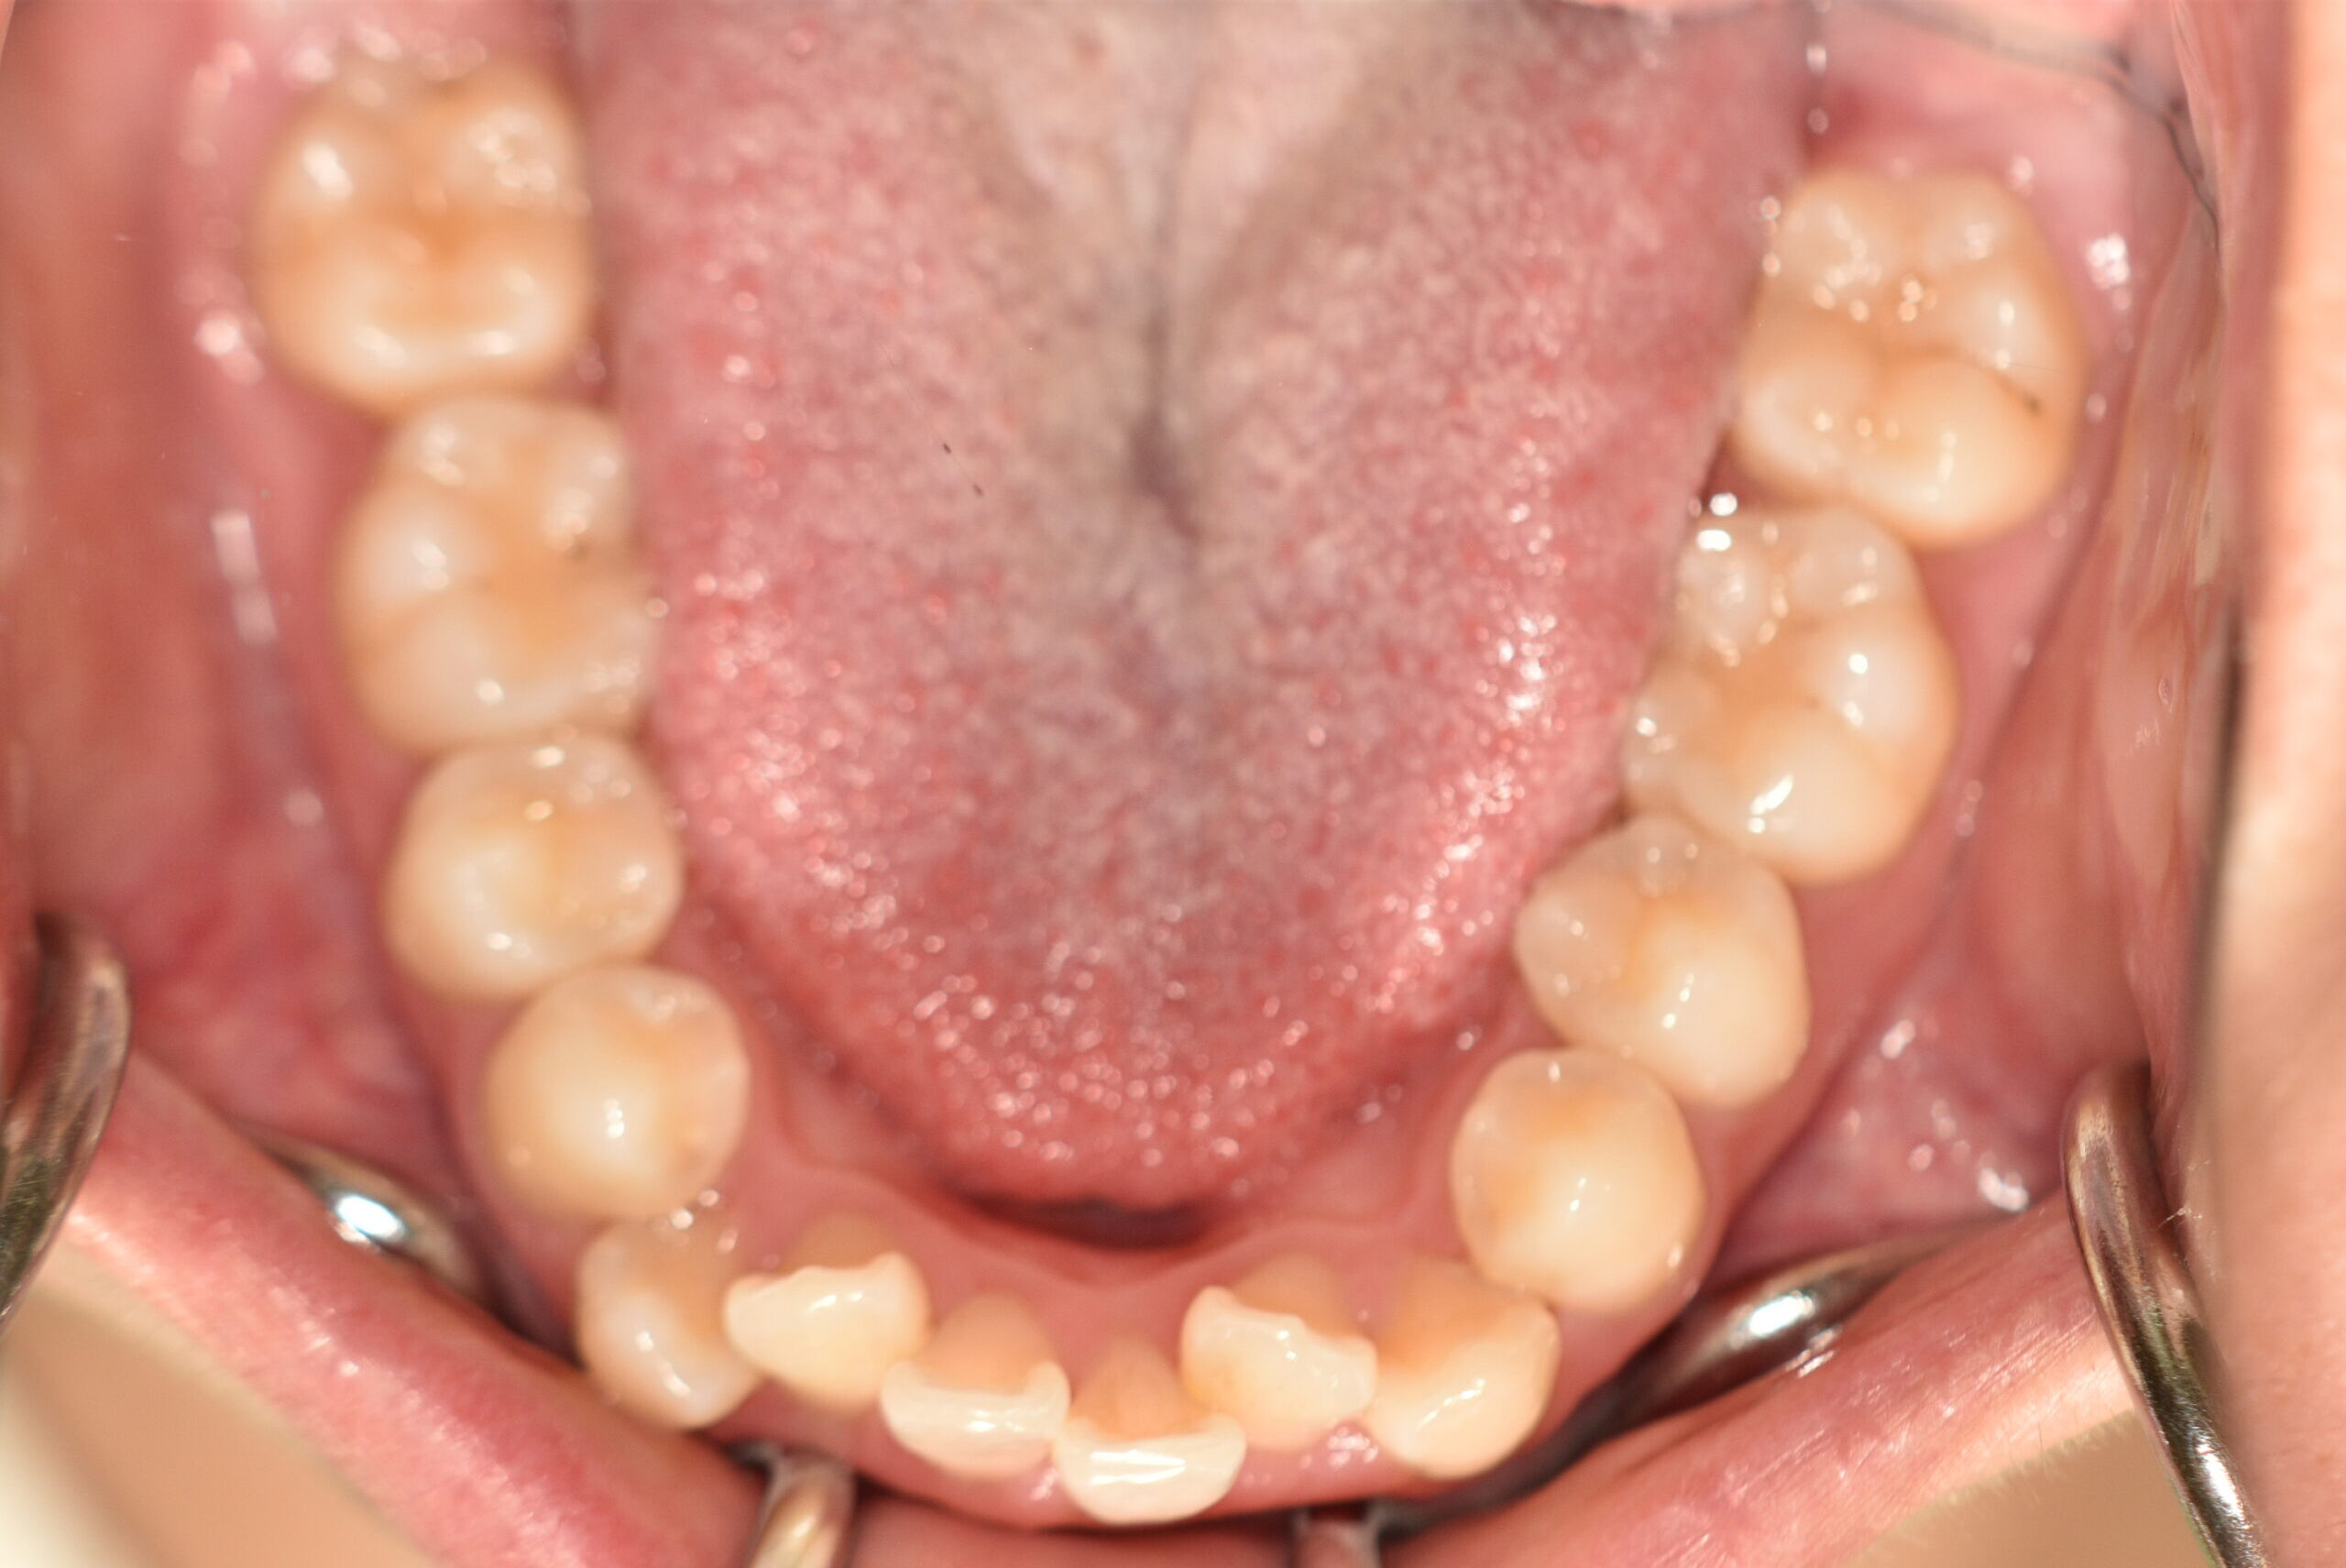

動的治療終了時

症例 症例 症例 症例 症例